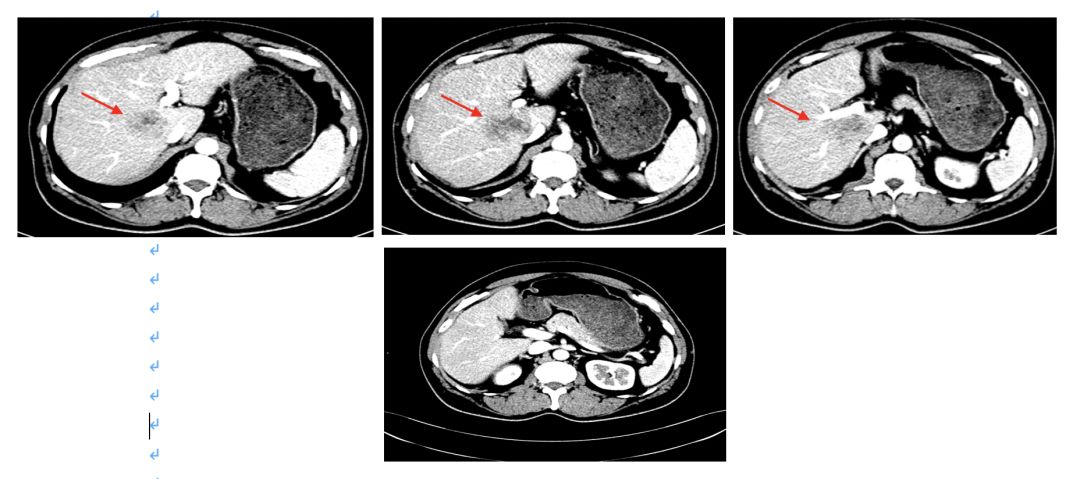

2015.1.22 肝脏MRI:肝右叶后段至尾叶肿块(大小4.9cm*5.9cm*5.4cm),肝右前叶近膈面0.9cm结节影,增强扫描边缘明显强化。

影像学评估 2015.4.7;

4周期评估肿瘤部分缩小;

2015.4.6 CEA下降至435ng/ml;

影像学评估:8周期化疗后,肝脏病灶缩小43%,疗效评价为部分缓解(PR)。